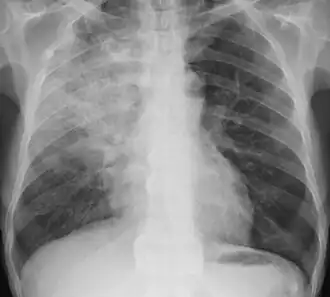

Radiography is the most common form of imaging used in the initial assessment of a foreign body presentation. Most patients receive a chest x-ray to determine the location of the foreign body.[2] Lateral neck, chest, and bilateral decubitus end-expiratory chest x-rays should be obtained in patients suspected of having aspirated a foreign body.[6] However, the presence of normal findings on chest radiography should not rule out foreign body aspiration as not all objects can be visualized.[2] In fact, up to 50% of cases can have normal findings on radiography.[7] This is because visibility of an object depends on many factors, such as the object's material, size, anatomic location and surrounding structures, as well as the patient's body habitus.[13] X-ray beams only show an object if that object's composition blocks the rays from traveling through, making it radiopaque and appearing lighter or white on the image. This also requires it to not be stuck behind something that blocks the beams first.[13] Objects that are radiopaque include items made of most metals except aluminum, bones except most fish bones, and glass. If the material does not block the x-ray beams it is considered radiolucent and will appear dark which prevents visualization.[13] This includes material such as most plastics, most fish bones, wood, and most aluminum objects.[13]

Signs on x-ray that are more commonly seen than the object itself and can be indicative of foreign body aspiration include visualization of the foreign body or hyperinflation of the affected lung.[13] Other x-ray findings that can be seen with foreign body aspiration include obstructive emphysema, atelectasis, and consolidation.[8]

While, x-ray can be used to visualize the location and identity of a foreign body, rigid bronchoscopy under general anesthesia is the gold-standard for diagnosis since the foreign body can be visualized and removed with this intervention.[2] Rigid bronchoscopy is indicated when two of the three following criteria are met: report of foreign body aspiration by the patient or a witness, abnormal lung exam findings, or abnormal chest x-ray findings.[2]